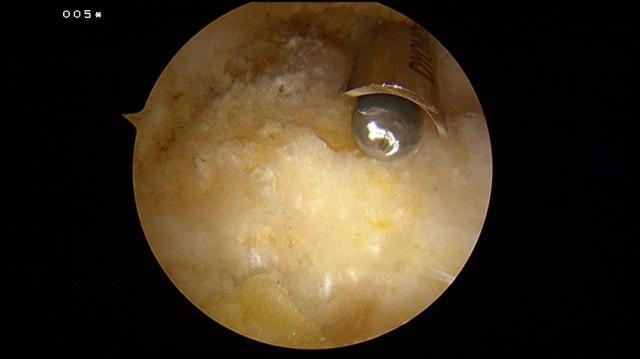

When the foot is brought into full dorsiflexion, the impingement site is determined.

A 4.0mm hooded arthroscopic burr is used to remove the Haglund’s exostosis. All of the time the opening of the burr is facing the bone. The foot is placed in full plantarflexion and the posterior superior bone rim can be removed.